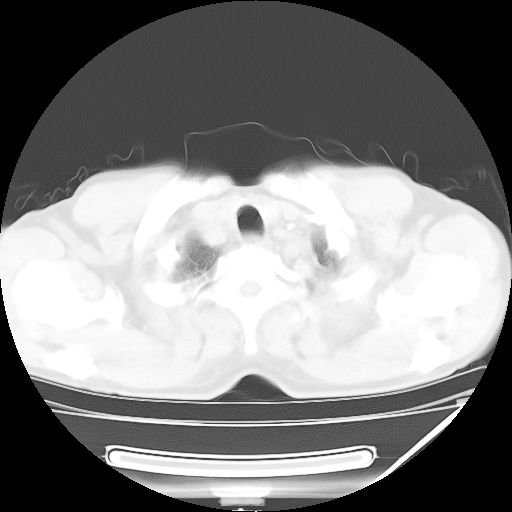

男,59岁,“结核性胸膜炎”30余年,胸部经常疼痛,多次x检查提示“肺部”炎症。腹部疼痛5日,b超提示:“肝内短管结石,余显示不清,建议进一步检查。”

两肺结核并右侧胸腔积液;脾脏、腹腔及腹膜后淋巴结结核[陈旧性];肝内胆管结石

胸部腹部都是结核(双肺。纵隔淋巴结,肝脏,脾脏,肠系膜)